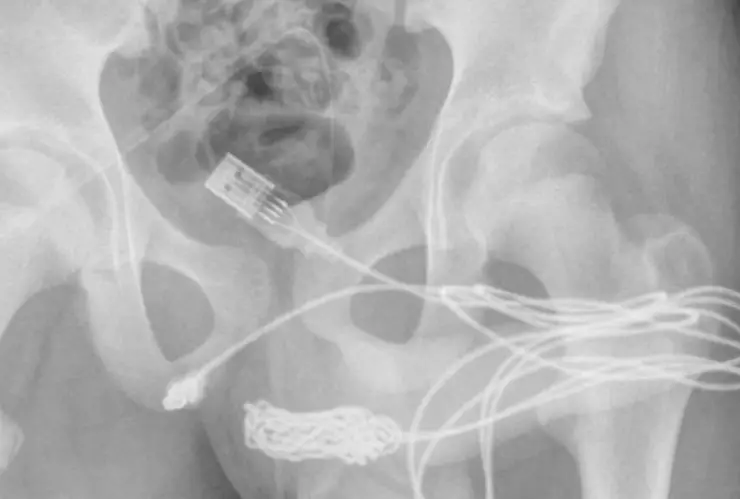

Los estudios de rayos X mostraron que los dos puertos del cable USB habían salido de la uretra, pero que la parte de en medio del cable se encontraba dentro de la uretra y se había enredado, por eso no podía sacarlo.